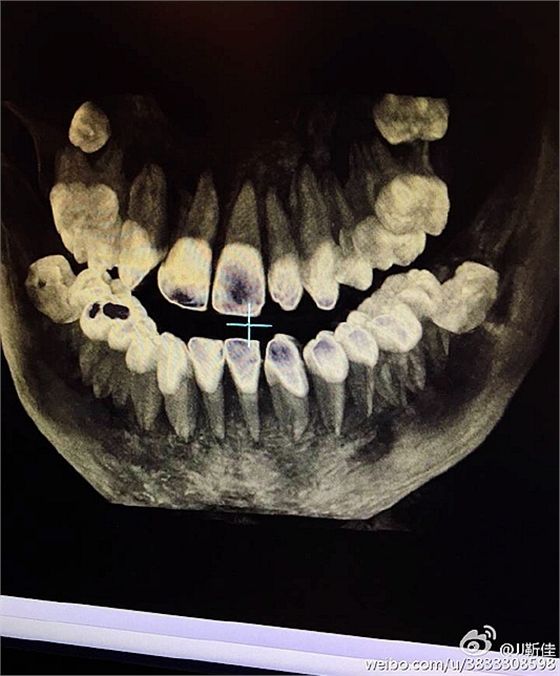

左下67缺失

今年的額外牙真多啊 男孩14周。

ct定位

額外牙拔除

好大的額外牙

術(shù)后拍片